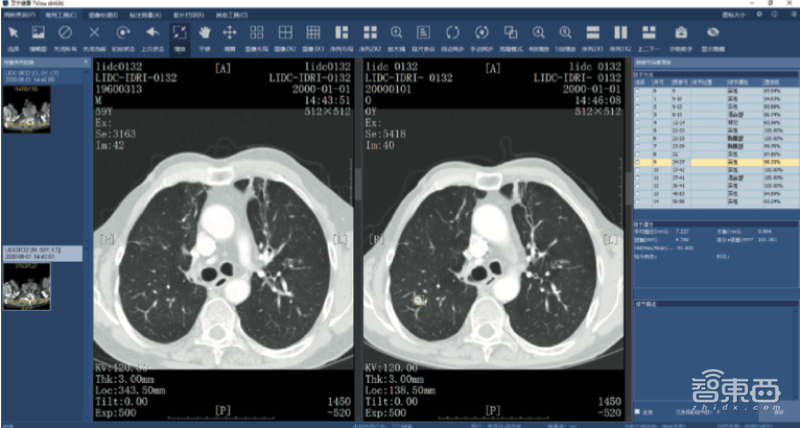

四、部署“AI+CT影像检测”,最高将推理速度提升30倍

英特尔、卫宁健康及AMAX 三方进行合作,推出了“AI+医学影像”解决方案。基于第二代英特尔至强可扩展处理器、OpenVINO工具套件、AMAX深度学习一体机,卫宁健康推出基于深度学习的医学影像AI产品。

为了验证该方案的性能表现,卫宁健康对该解决方案进行了测试。系统运行Linux Pytorch Default:numa off和Linux Pytorch Optimized:numa mapped两个任务。OpenVINO工具套件采取三种配置。每一个任务均为 36个逻辑内核分配了36个子任务。

测试数据显示,在分割、检测、去假阳性这三种任务中,OpenVINO工具套件将推理速度提升了10~30倍。